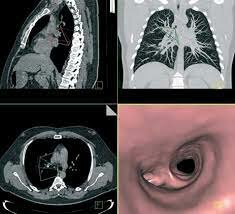

• Tomografía Computada Multicorte

Tomografía Computada Multicorte

Sale al mercado el primer equipo de TAC multicorte, el cual ya contaba con varias filas de detectores

• Sistema PET/TC

Sistema PET/TC

Surge la tomografía por emisión de positrones que utiliza pequeñas cantidades de materiales radioactivos denominados radiosondas o radiofármacos, una cámara especial y una computadora para evaluar las funciones de tejidos y órganos.